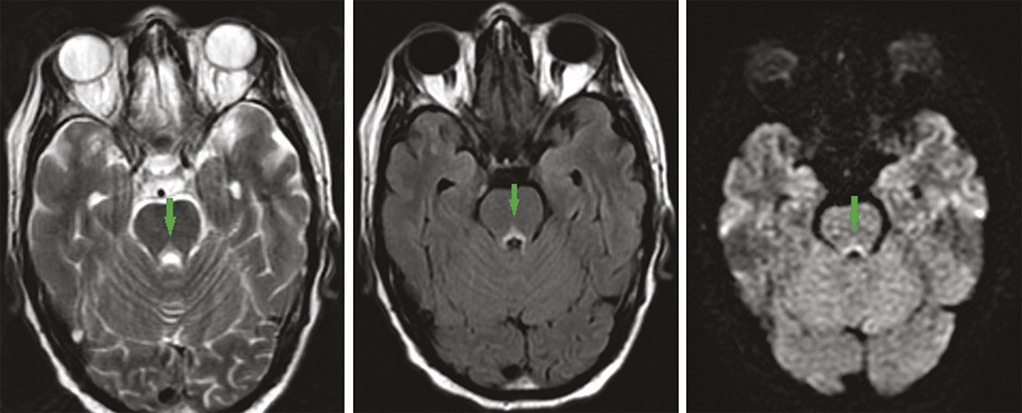

Ce patient de 49 ans, ayant bénéficié d’une duodénopancréatectomie céphalique pour un ampullome vatérien, était admis pour des vomissements incoercibles apparus en postopératoire immédiat, rebelles au traitement, et mis sous nutrition parentérale. Une semaine plus tard apparaissait un syndrome confusionnel avec apathie et hypersomnie. L’imagerie par résonance magnétique (IRM) montrait des hypersignaux T2, Flair et diffusion, bilatéraux et symétriques du thalamus postéromédian, périventriculaires du troisième ventricule et périaqueducaux en hypersignal (fig. 1, 2 et 3 ). Devant cet aspect en imagerie, associé aux vomissements prolongés, à l’alimentation parentérale et aux troubles neuropsychiques, une encéphalopathie de Gayet-Wernicke était évoquée, et le patient mis sous thiamine, avec une bonne évolution.

L’encéphalopathie de Gayet-Wernicke est une urgence médicale due à une carence aiguë et massive en vitamine B1.1 En dehors de l’alcoolisme, ses facteurs de risque sont : chirurgie gastro-intestinale, vomissements chroniques, nutrition parentérale prolongée, jeûne prolongé, malnutrition, anorexie mentale, chimiothérapie, sida.2 Elle se manifeste par une triade associant à divers degrés des troubles neuropsychiques (confusion, apathie, bradypsychie, hypersomnie), des troubles oculomoteurs et des troubles de l’équilibre. L’IRM cérébrale objective classiquement des hypersignaux symétriques dans les séquences pondérées T2, Flair et parfois une diffusion, de part et d’autre du troisième ventricule, des noyaux thalamiques postéromédiaux, des corps mamillaires, et de la région périaqueducale.1 Son traitement est fondé sur l’administration de thiamine.